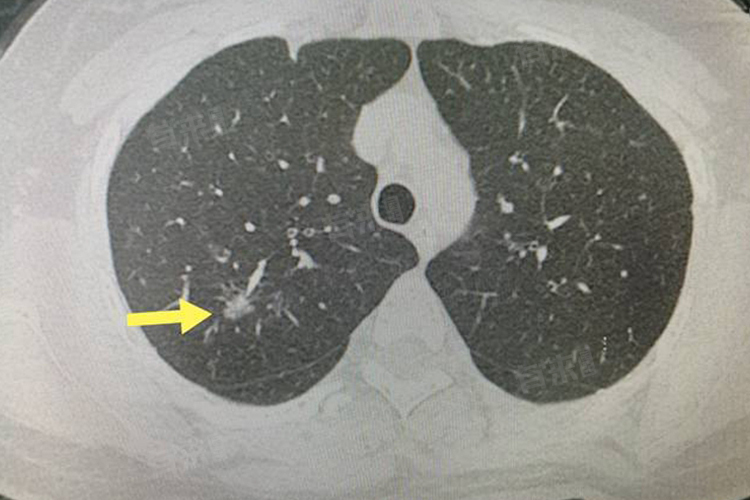

5、早期肺癌:表现为局限性的磨玻璃影,患者可能没有明显症状,一般不会自行消失,需要密切观察,定期复查。如果结节有增大、密度增高或出现实性成分等变化,可能需要手术治疗。患者要戒烟,避免接触有害气体和粉尘。